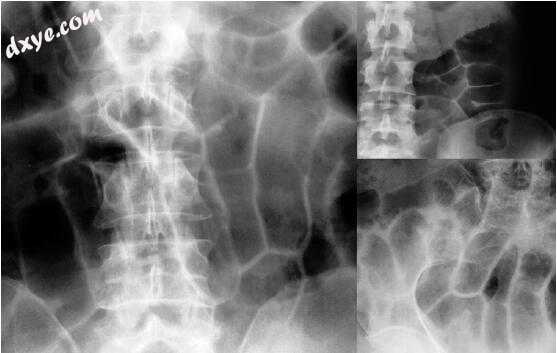

图5.16a-f。小肠梗阻。超音波和放射线综合。a-d“基本系列”射线照片。回肠空肠扩张。可察觉到的绞窄框架。气液停滞。许多强制性环状襞收缩。右侧空肠和左侧回肠的异常位置增加了小肠扭转的可能。含气环显示规则和薄壁。对于下腹部不透明的含液体的袢圈,无法进行形态学和诊断上的判断。幸运的是,液体充当了声学窗口,因此允许超声和普通胶片之间的集成。(续)

16-2.jpg

16-3.jpg

e,f超声波检查。 扩张的回肠环具有液体含量和薄壁。 由于极端的腔内张力导致扁平瓣膜狭窄。 存在游离腹膜液(tanga sign)。 手术显示粘连带小肠小肠扭转。 (Grassi R等人的图5.16e(2004)在成人小肠梗阻的临床评估中通过超声检查检测到的肠环之间游离液的相关性.Eur J Radiol 50:5-14,经许可转载)